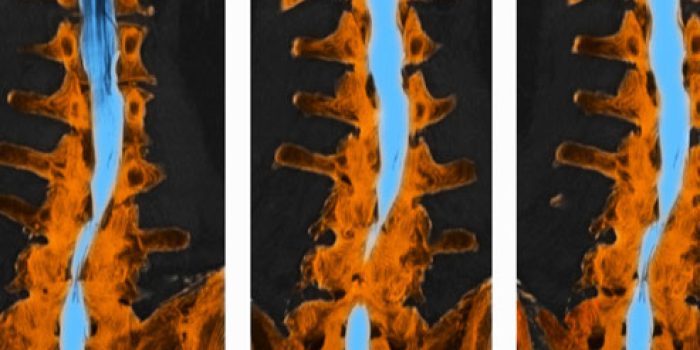

حال به بررسی راههای تشخیص این بیماری میپردازیم…

راه های تشخیص کانال نخاع